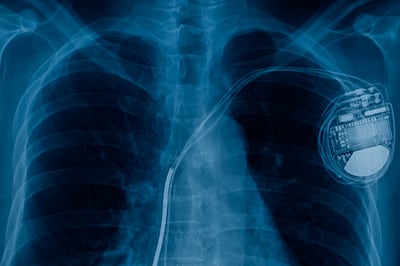

What about mobile phones interfering with pacemakers and other implanted medical devices? RF can interact with some electronic medical devices, such as implanted defibrillators, by causing electromagnetic interference (EMI). While there is no definitive evidence as yet to suggest that mobile phones pose a significant health problem for pacemaker wearers, some precautions are warranted. In order to avoid the risk of stopping a pacemaker from delivering the stimulating pulses that regulate the heart’s rhythm or causing the pacemaker to deliver the pulses irregularly, the following is good advice:

Hold the phone to the ear opposite the side of the body where the pacemaker or defibrillator is implanted to add some extra distance between the device and the phone.

- Avoid placing a turned-on phone next to the pacemaker/defibrillator implant. For example, don’t carry the phone in a shirt or jacket pocket directly over the implanted device.

- Aim to keep your phone or smartwatch at least six inches away from the implanted cardiac device.